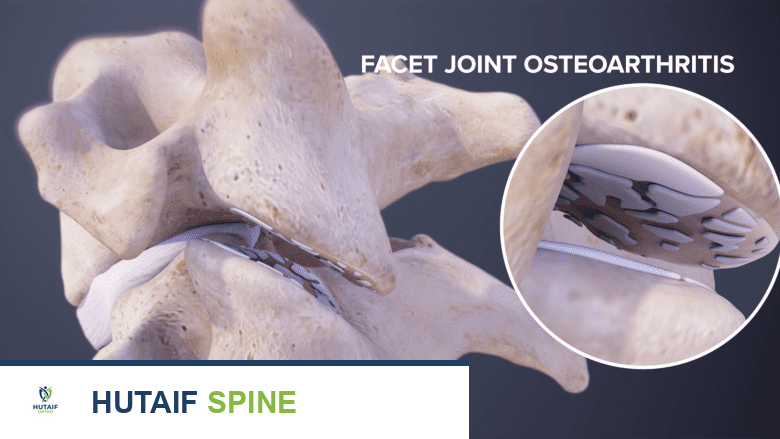

المفاصل الوجيهية، أو المفاصل الفقرية (Facet Joints)، هي مفاصل صغيرة تقع على جانبي كل فقرة. هذه المفاصل تربط الفقرات ببعضها البعض وتسمح بحركة العمود الفقري مثل الانحناء والدوران والتمدد. كل مفصل وجيهي محاط بكبسولة مليئة بسائل زلالي يقلل الاحتكاك ويسمح بالحركة السلسة. مثل أي مفصل آخر في الجسم، يمكن أن تتأثر هذه المفاصل بالتهاب المفاصل (الخشونة)، الإصابات، أو التآكل مع التقدم في العمر، مما يؤدي إلى الألم والتصلب.

- التهاب المفاصل التنكسي (الخشونة): يُعد هذا السبب الأكثر شيوعًا. مع التقدم في العمر، تتآكل الغضاريف التي تغطي أسطح المفاصل الوجيهية، مما يؤدي إلى احتكاك العظام ببعضها البعض، والتهاب، وتكون نتوءات عظمية (Osteophytes). هذا التآكل يسبب ألمًا وتصلبًا في العمود الفقري.

يكشف فحص الرنين المغناطيسي عن تلف والتهاب في المفاصل الوجيهية.